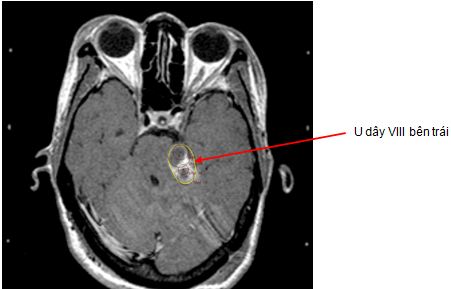

Trường hợp 2: Bệnh nhân nam, 56 tuổi. Được chẩn đoán là u dây thần kinh số VIII bên trái có các triệu chứng ban đầu: đau đầu, nôn, tê nửa mặt trái. Trên hình ảnh MRI sọ não trước và sau 1 năm, sau 2 năm xạ phẫu bằng dao gamma quay cho thấy khôi u đã mất. Các triệu chứng lâm sàng ban đầu đều hết, bệnh nhân không bị liệt mặt, sinh hoạt bình thường, chất lượng cuộc sống tốt.

Trước điều trị: u dây VIII bên       Sau điều trị 1 năm: u hoại tử               Sau 2 năm: u tiêu biến

trái kích thước 1,8cm

Hình 3: Hình ảnh MRI u dây VIII trước và sau xạ phẫu gamma quay